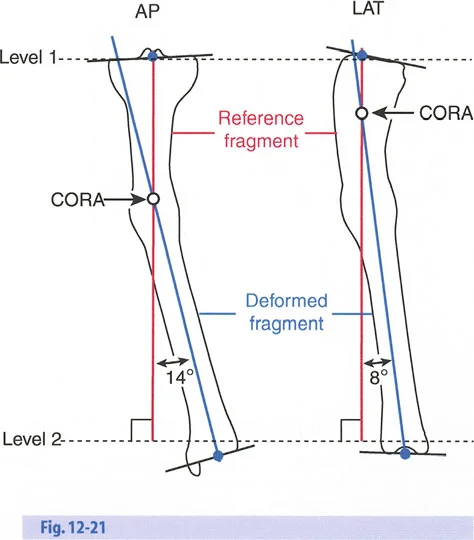

- الأشعة السينية الطويلة للطرفين (Long-leg Standing X-rays): هذه الأشعة ضرورية لتقييم المحور الميكانيكي للطرف بالكامل أثناء الوقوف. تسمح بتحديد مركز دوران الانحراف (CORA) بدقة، وهو النقطة التي يجب أن تتمحور حولها عملية التصحيح.

القياسات الهندسية:

- باستخدام صور الأشعة السينية الطويلة، يقوم الأستاذ الدكتور محمد هطيف بإجراء قياسات هندسية دقيقة لتحديد الزوايا غير الطبيعية (مثل mLDFA و MPTA)، ومقدار القصر، ودرجة الدوران، وأي انحرافات في المحور الميكانيكي. هذه القياسات هي الأساس لتخطيط الجراحة بدقة متناهية.

تحدي مركز دوران الانحراف (CORA) القريب من المفصل

لمطابقة مفصلة المثبت الخارجي مع المستوى الدقيق لمركز دوران الانحراف (CORA)، يجب غالبًا بناء المفصلة فوق أو تحت مستوى الحلقة الفعلية. يُعرف هذا في مبادئ بالي باسم تجميع المفصلة القريبة من المفصل (juxta-articular hinge assembly).

إذا كان مركز دوران الانحراف (CORA) يقع بالقرب من خط المفصل، فإن وضع حلقة إليزاروف القياسية عند هذا المستوى بالضبط مستحيل دون انتهاك مساحة المفصل أو شد الهياكل الكبسولية الحيوية. لذلك، يتم تثبيت الحلقة المرجعية بالعظم الكثيف أو العظم الطويل المتاح، ويتم بناء آلية المفصلة باستخدام قضبان ملولبة، ولوحات توصيل، ودعامات. ثم يتم "إنزالها" (أو رفعها) لتتطابق تمامًا مع مركز دوران الانحراف (CORA) الهندسي الحقيقي.